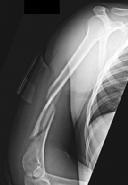

Question 20:

A 6-year-old boy falls from the monkey bars and sustains a completely displaced, extension-type supracondylar humerus fracture (Gartland Type III). During your neurologic examination in the emergency department, you ask the child to make an 'OK' sign with his hand, but he is unable to flex the interphalangeal joint of his thumb and the distal interphalangeal joint of his index finger. Which nerve is most likely injured?

Correct Answer: Anterior interosseous nerve (AIN)

Explanation:

The anterior interosseous nerve (AIN), a motor branch of the median nerve, is the most commonly injured nerve in extension-type supracondylar humerus fractures (particularly those that displace posterolaterally). It innervates the flexor pollicis longus (FPL), the radial half of the flexor digitorum profundus (FDP to index and middle fingers), and the pronator quadratus. An AIN palsy clinically presents as the inability to form an 'OK' sign (pincer grasp) due to weakness of the FPL and FDP.